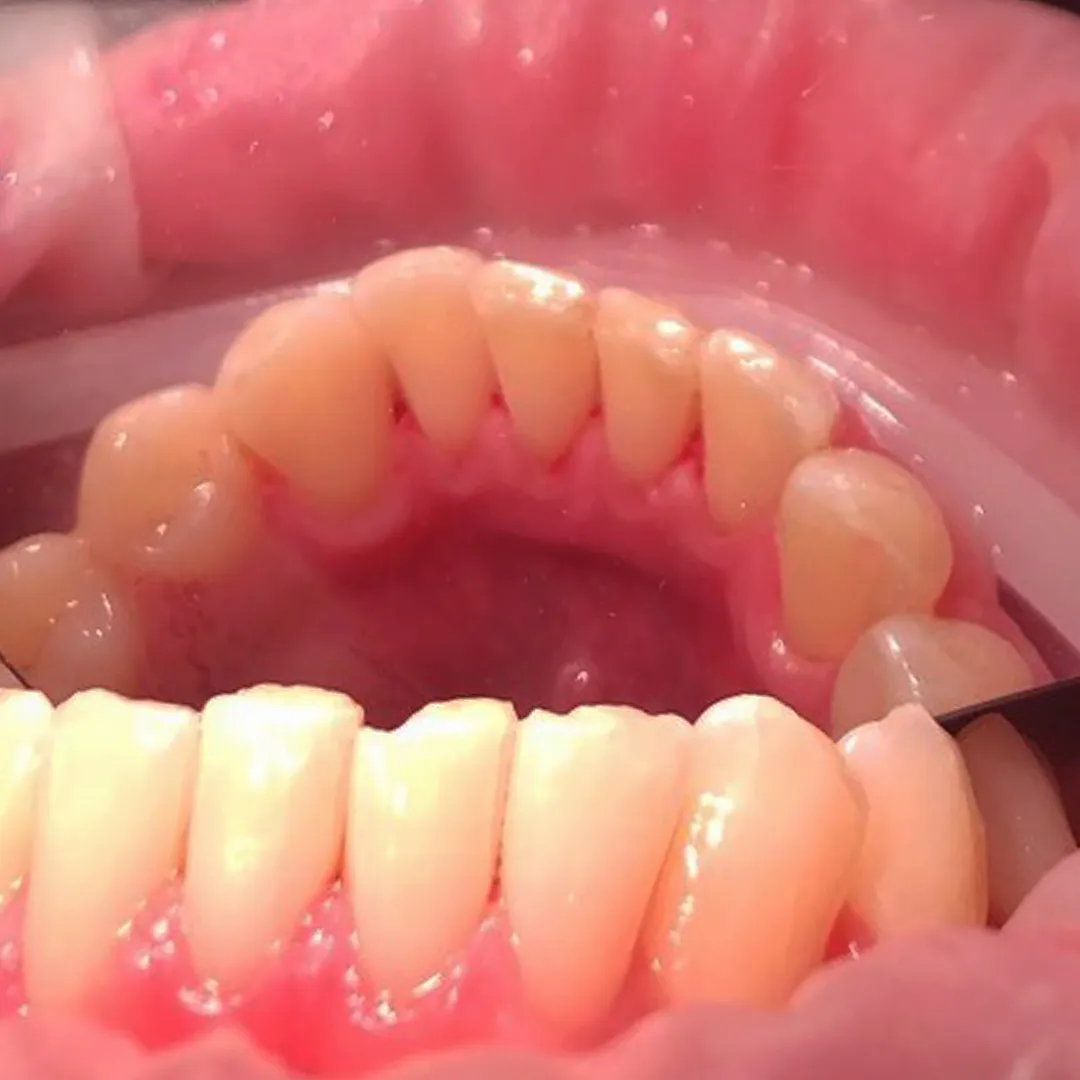

До и после лечения

Родители пациента обратились в «Стоматологию Комфорта» для исправления неправильного прикуса у ребёнка 11-и лет. Врач-ортодонт Резниченко Анна Васильевна провела осмотр и установила, что у пациента наблюдается суперпозиция 23 зуба и вертикальная резцовая окклюзия. Врачом было принято решение о целесообразности лечения съёмным аппаратом-ортокорректором Occlus-o-Guide.

Ортокорректор Occlus-o-Guide производства США предотвращает нарушение окклюзии зубных рядов в сменном прикусе. Аппарат ускоряет процесс выравнивания зубных единиц у детей, а также способствует улучшению профиля ребёнка. Occlus-o-Guide предназначен для лечебных ортодонтических упражнений. Его применение направляет и смещает прорезывающиеся постоянные зубы к нормальной окклюзии.